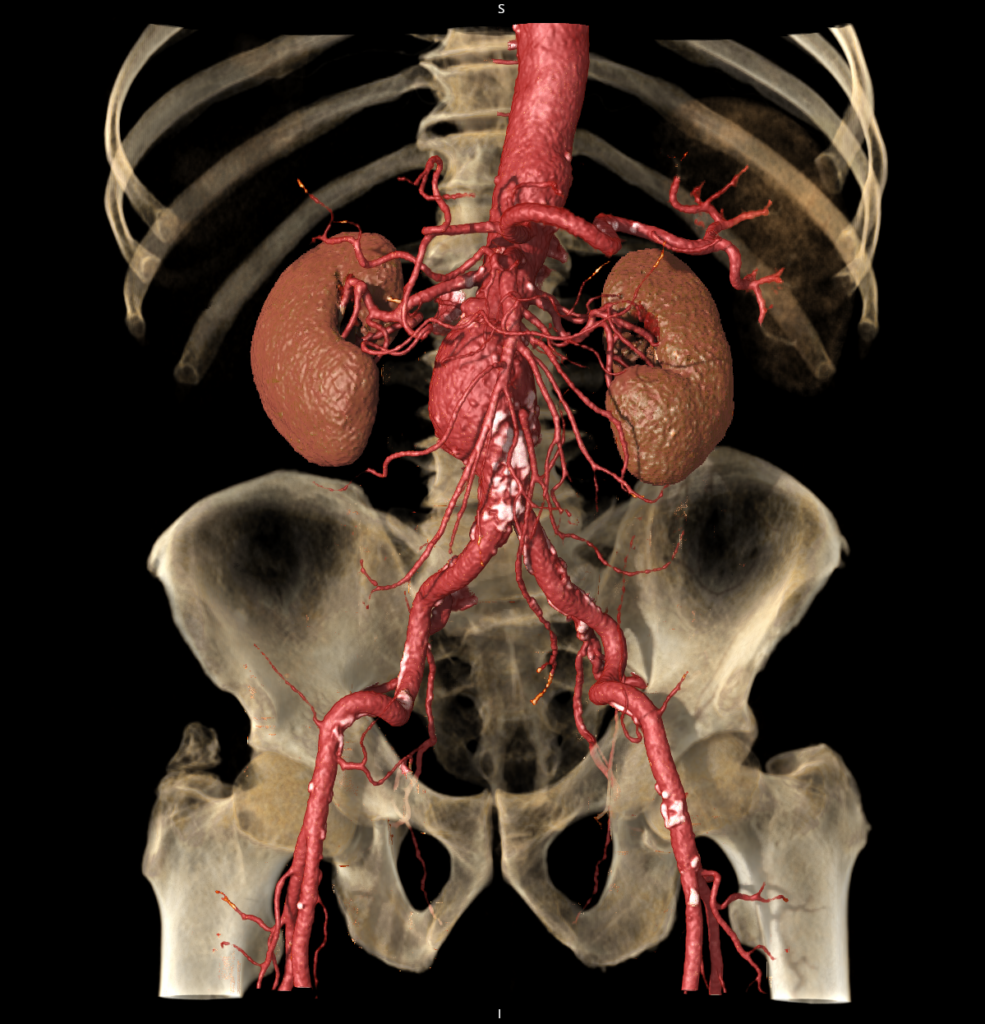

CT Aorta Analysis

CT Aorta Analysis enables users to visualize and evaluate the aorta vasculature.